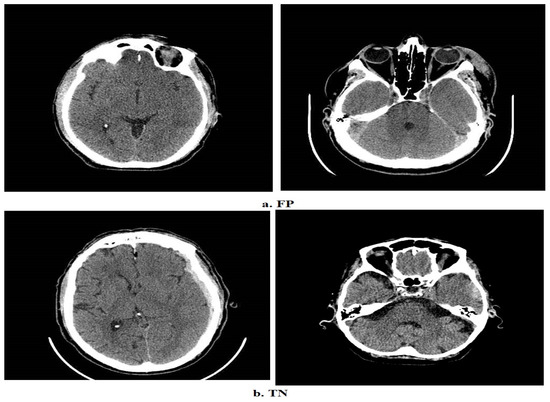

4.3. Results of the Deep Learning